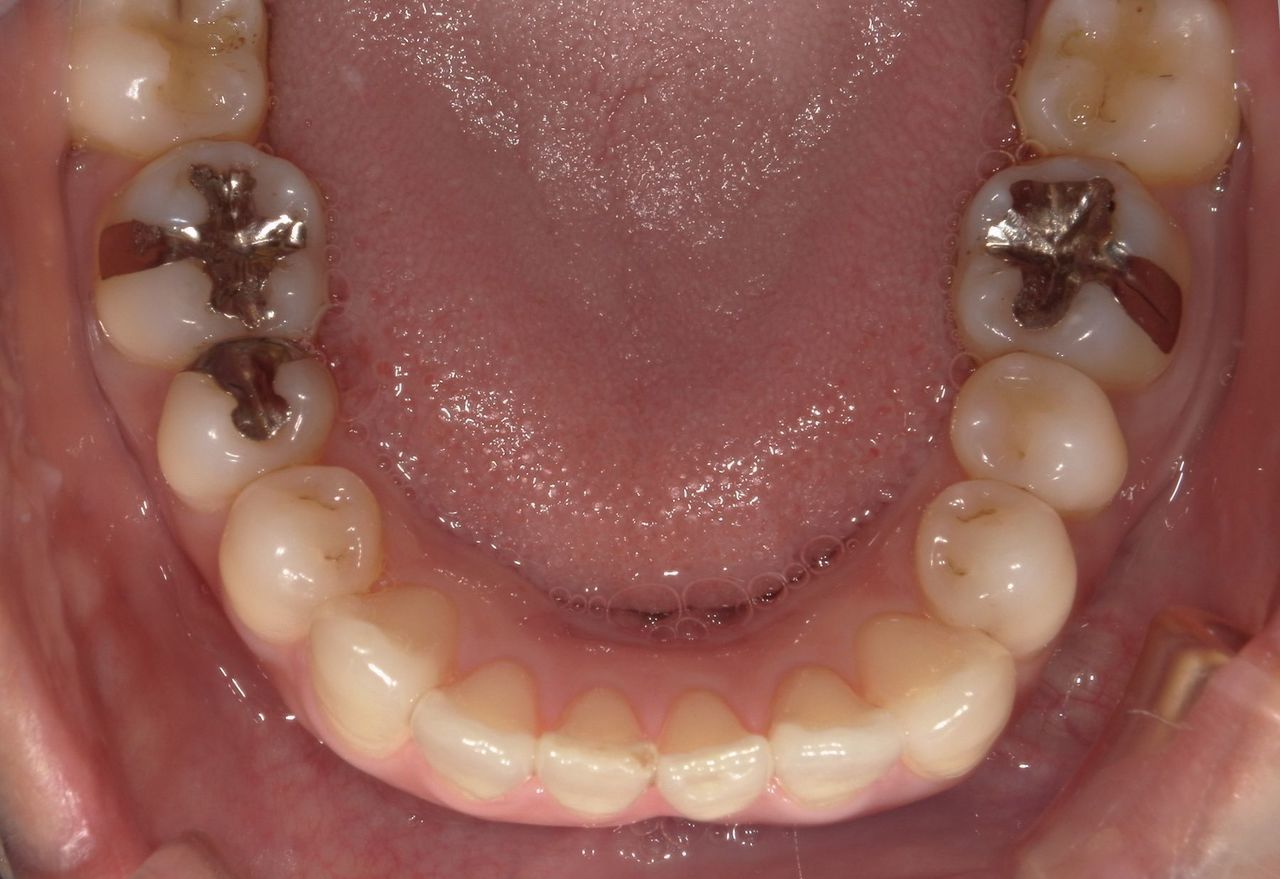

当院ではCADCAM(キャドカム)装置を導入しています。キャドカムとは硬質レジンのブロックから機械で詰め物を削り出す装置です。

銀歯は目立つから嫌だという方には、保険診療で白い詰め物が可能になりました。歯の欠損が大きい場合やブリッジなどは保険適応外になるため、より強度が強いセラミックやジルコニアをお勧めします(自費治療)。

古くなった銀歯は虫歯になりやすく、成分が溶け出してアレルギーの原因になることから、当院では銀歯のやり替えをお勧めしています。